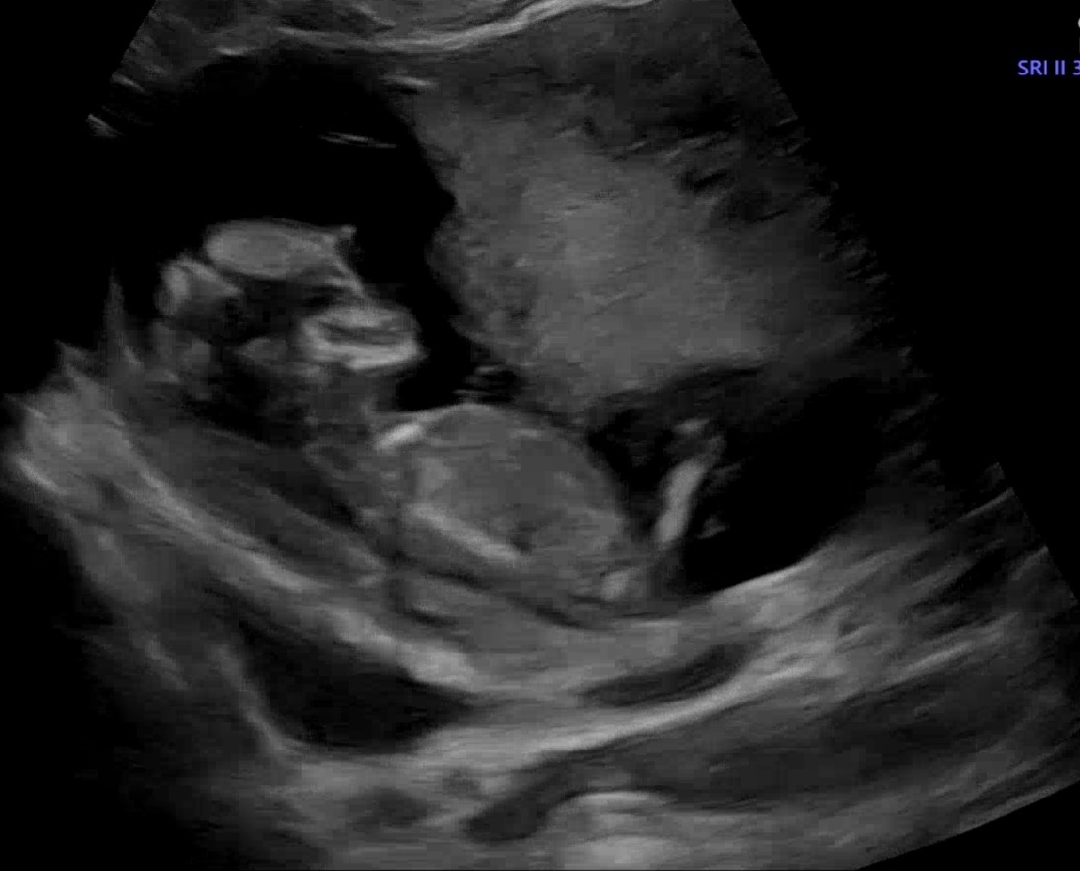

12주 검사 각도법 봐주세요

아들일까요 딸일까요?? ㅜㅜ